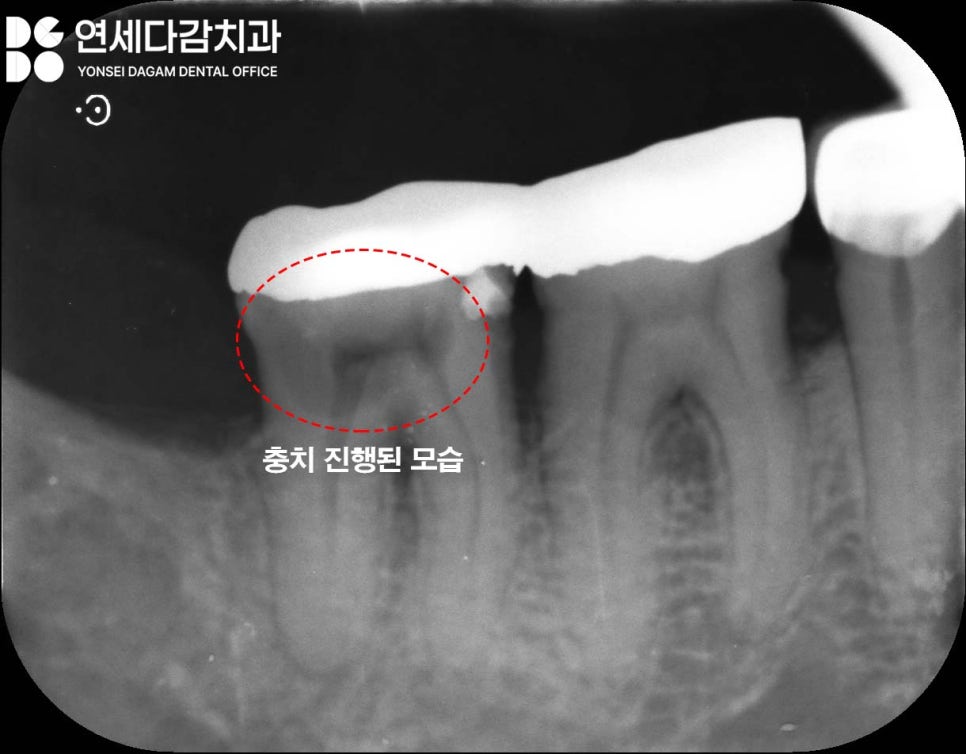

치근 우식

크라운 내부에서 발견될 수 있는

또 다른 문제는 치근 충치입니다.

크라운 하방으로 치아 뿌리 부분인

치근에 충치가

깊게 생기는 경우가 있습니다.

이는 보존 가능성이 떨어지는

상황일 수밖에 없는데,

이유를 가락시장역 치과 에서 설명드리자면

우선, 치료 접근이 어렵습니다.

치근은 잇몸 아래 깊숙이 위치하여

기구가 닿기 어렵고 시야 확보도

안 될뿐더러

치료를 해도 예후가 좋지 않습니다.

치근 부위는 법랑질이 아닌 백악질로

덮여있어 충치 진행이 빠르고 치료

후에도 재발 위험이 높습니다.

치근에 충치가 깊으면 치아를 지지하는

기초가 무너진 것과 같습니다.

건물의 기초가 썩으면 위의 구조물을

유지할 수 없듯이 치아도 마찬가지입니다.

이런 경우 발치 후 임플란트로 기능을

회복하는 것이 더 나은 대안이 됩니다.